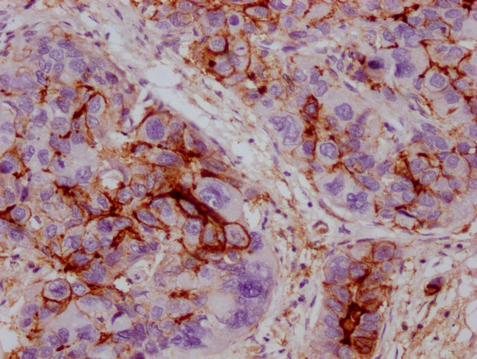

IHC image of CSB-MA211660 diluted at 1:100 and staining in paraffin-embedded human liver cancer performed on a Leica BondTM system. After dewaxing and hydration, antigen retrieval was mediated by high pressure in a citrate buffer (pH 6.0). Section was blocked with 10% normal goat serum 30min at RT. Then primary antibody (1% BSA) was incubated at 4°C overnight. The primary is detected by a Goat anti-mouse IgG polymer labeled by HRP and visualized using 0.05% DAB.